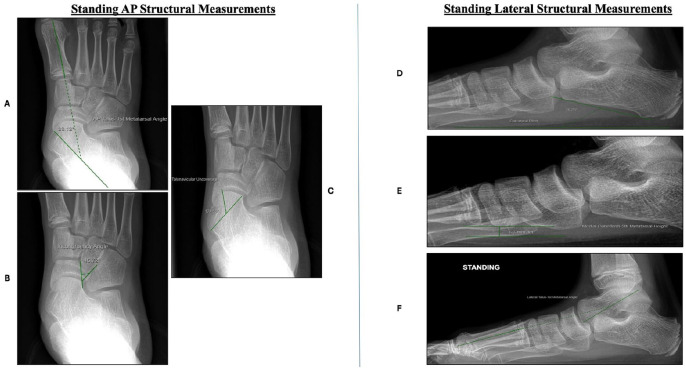

Methods: Children aged 8-18 who underwent CLO for painful FF correction were included. Retrospective chart review for PROMIS scores of pain and mobility were collected. Preoperative PROMIS scores were compared to PROMIS scores collected within 6-12 months postoperatively. Five PROMIS points was determined to be a minimal clinically significant difference, as this is half of the SD of the PROMIS metric. Preoperative and postoperative AP/lateral talo-first metatarsal angles were collected and compared. The patients with residual pain (PROMIS >55) after CLO were evaluated, and the effect of potential factors on residual postoperative pain was assessed.